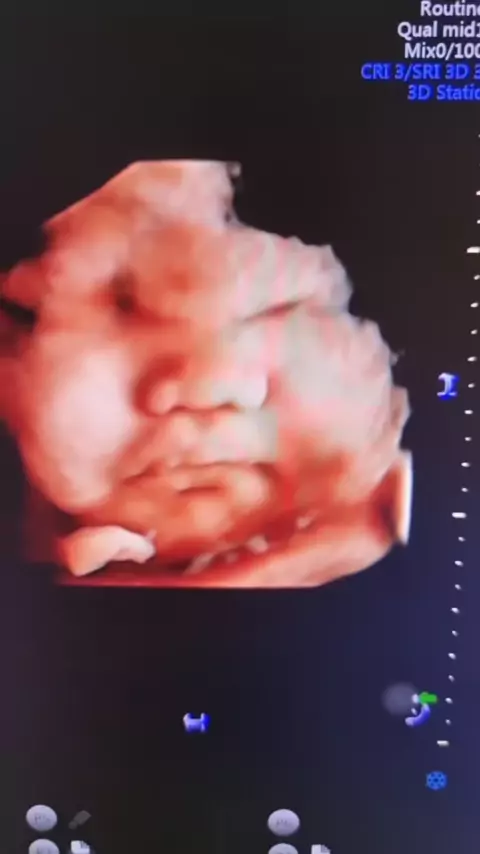

⚠️ USG 2D atau 3D4D ? UDA TAU KAN JAWABANNYA.. TAPI MEMANG KADANG USG DENGAN KEMAMPUAN 3D4D MEMILIKI RESOLUSI YANG BAIK.. SEHINGGA 2D AJA LEBIH TAJAM DAN LEBIH DETAIL MELIHAT ORANG YANG AGAK SULIT SEPERTI JANTUNG.#USG#usg4dimensi#usg2dimensi#usg3d#usgbayi#kontrolhamil